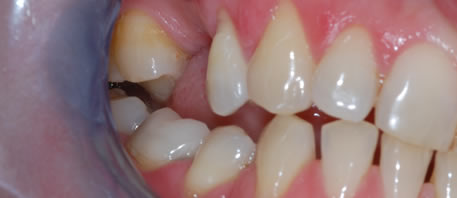

Before Dental Implant

dental implants northern ireland

After Dental Implant